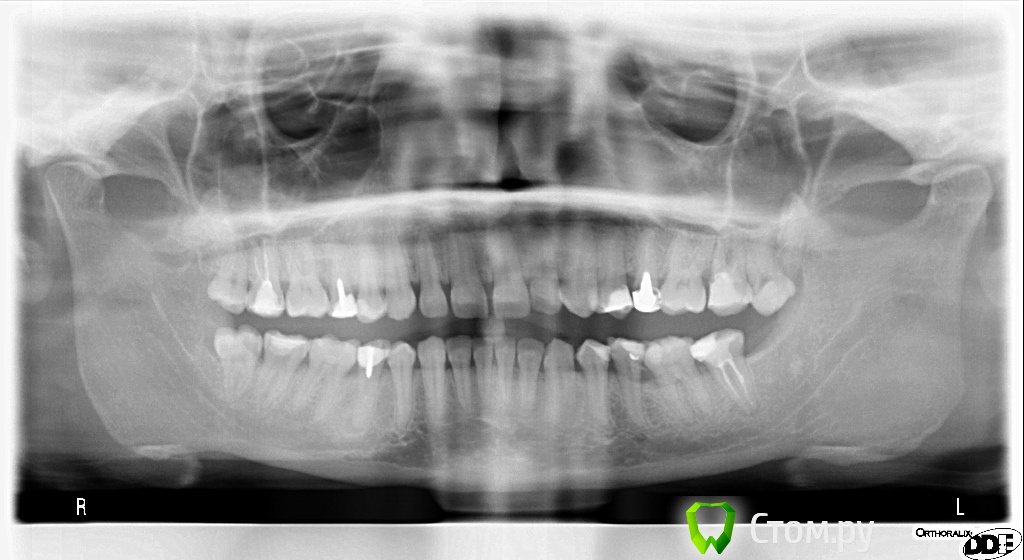

alena341 Опубликовано 9 декабря, 2013 Поделиться Опубликовано 9 декабря, 2013 Здравствуйте, хотела узнать ваше мнение по проблеме: На следующий день после замены штифта в 25 зубе, началось легкое подергивание нижнего века правого глаза, которое периодически возобновляется до сих пор, уже несколько месяцев. Знаю, что это скорее всего совпадение, но все же хотела узнать мнение специалистов. Могли ли стоматологические операции спровоцировать появление подергивания нижнего века? Выкладываю два панорамных снимка со старым и новым штифтом, по которым видно, что новый штифт существенно длиннее. При смене штифта перепломбировки каналов не производилось. Лечение проводилось под местной анестазией. При следующем посещении была также произведена смена коронки. Спасибо за ответ!с уважением,Ольга Ссылка на комментарий